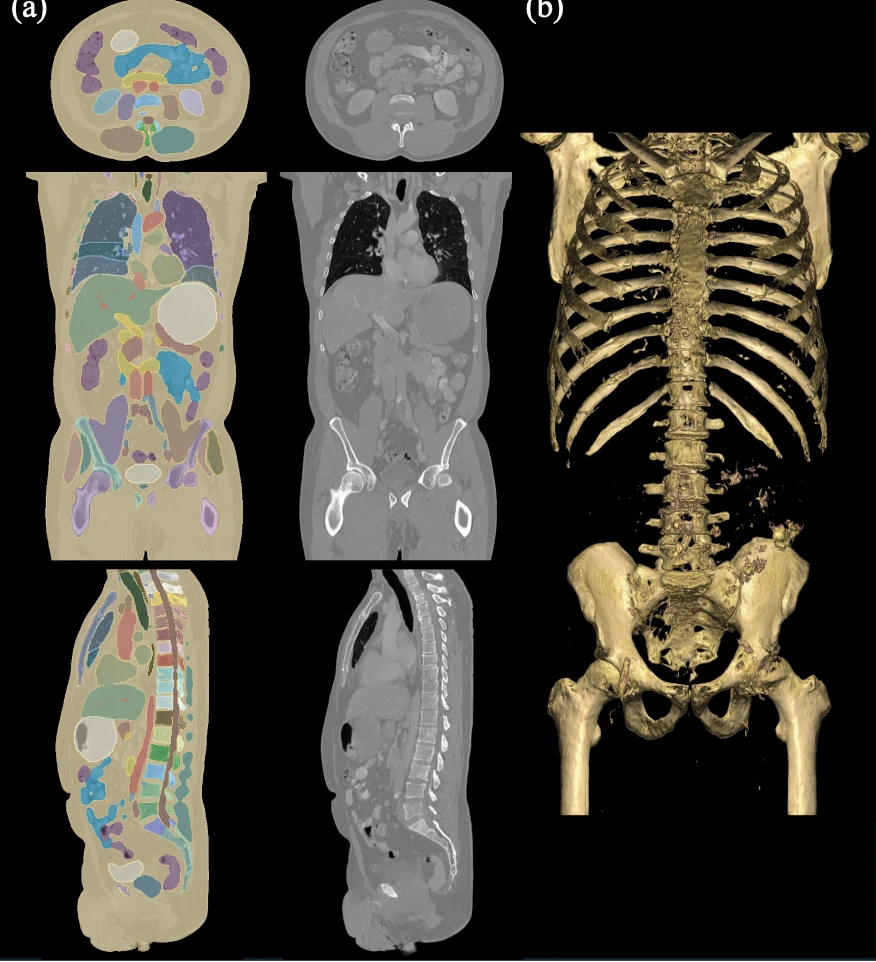

The experimental findings demonstrate that MAISI can generate lifelike, anatomically precise images across various body regions and conditions (See the image below).

Figure 1: (a) A high-resolution CT scan generated by MAISI with its segmentation overlay, shown in axial, sagittal, and coronal views. (b) A 3D rendering focused on bone structures, highlighting the realism of the generated scan.2